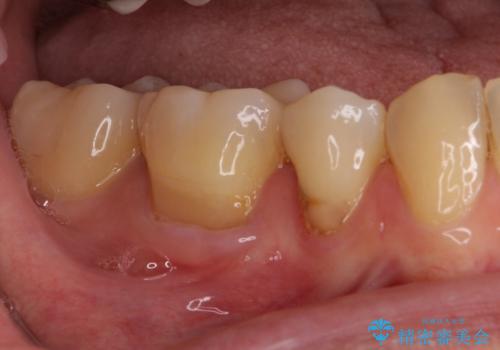

矯正治療後には、下顎臼歯の目立つ銀歯をセラミックインレーにて修復治療を行いました。

口を開けたときに金属が見えなくなり、患者様には大変満足していただきました。